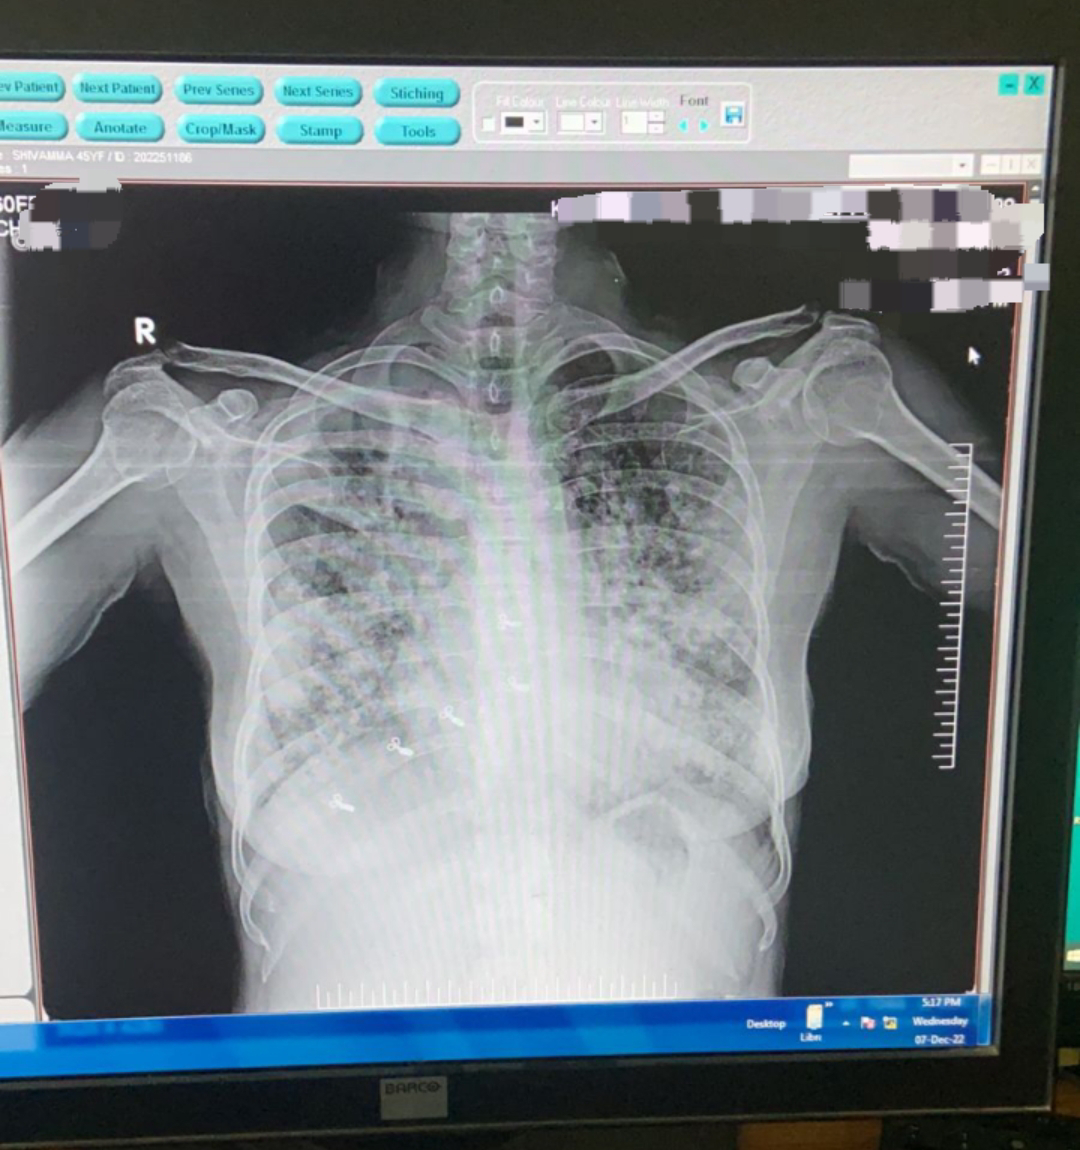

A 45 year old female patient came to OPD with chief c/o fever since 10days, cough and breathlessness since 5 days,no palpitations,no chest pain o up by Drr chest tightness,no h/o hemoptysis,complains of weightloss 5kgs during 2 months.Had 1 episode of vomiting and 4 episodes of loose stools yesterday

Patient was apparently asymptomatic 10 days back from when she had fever which is associated with chills and rigors,high grade ,intermittent and with diurnal variation,increasing during night and subsided by day.Cough is not productive and occasional.Breathlessness insidious onset and MMRC grade 3 associated with wheeze

Decreased resonance on mammary and infrascapular areas

Crepts in mammary and infra scapular areas of both lungs

Decreased breath sounds on mammary area of rt lung

Chest x ray

CBNAAT:- tested positive for AFB

Septic shock secondary to pneumonia

? Tuberculosis infection